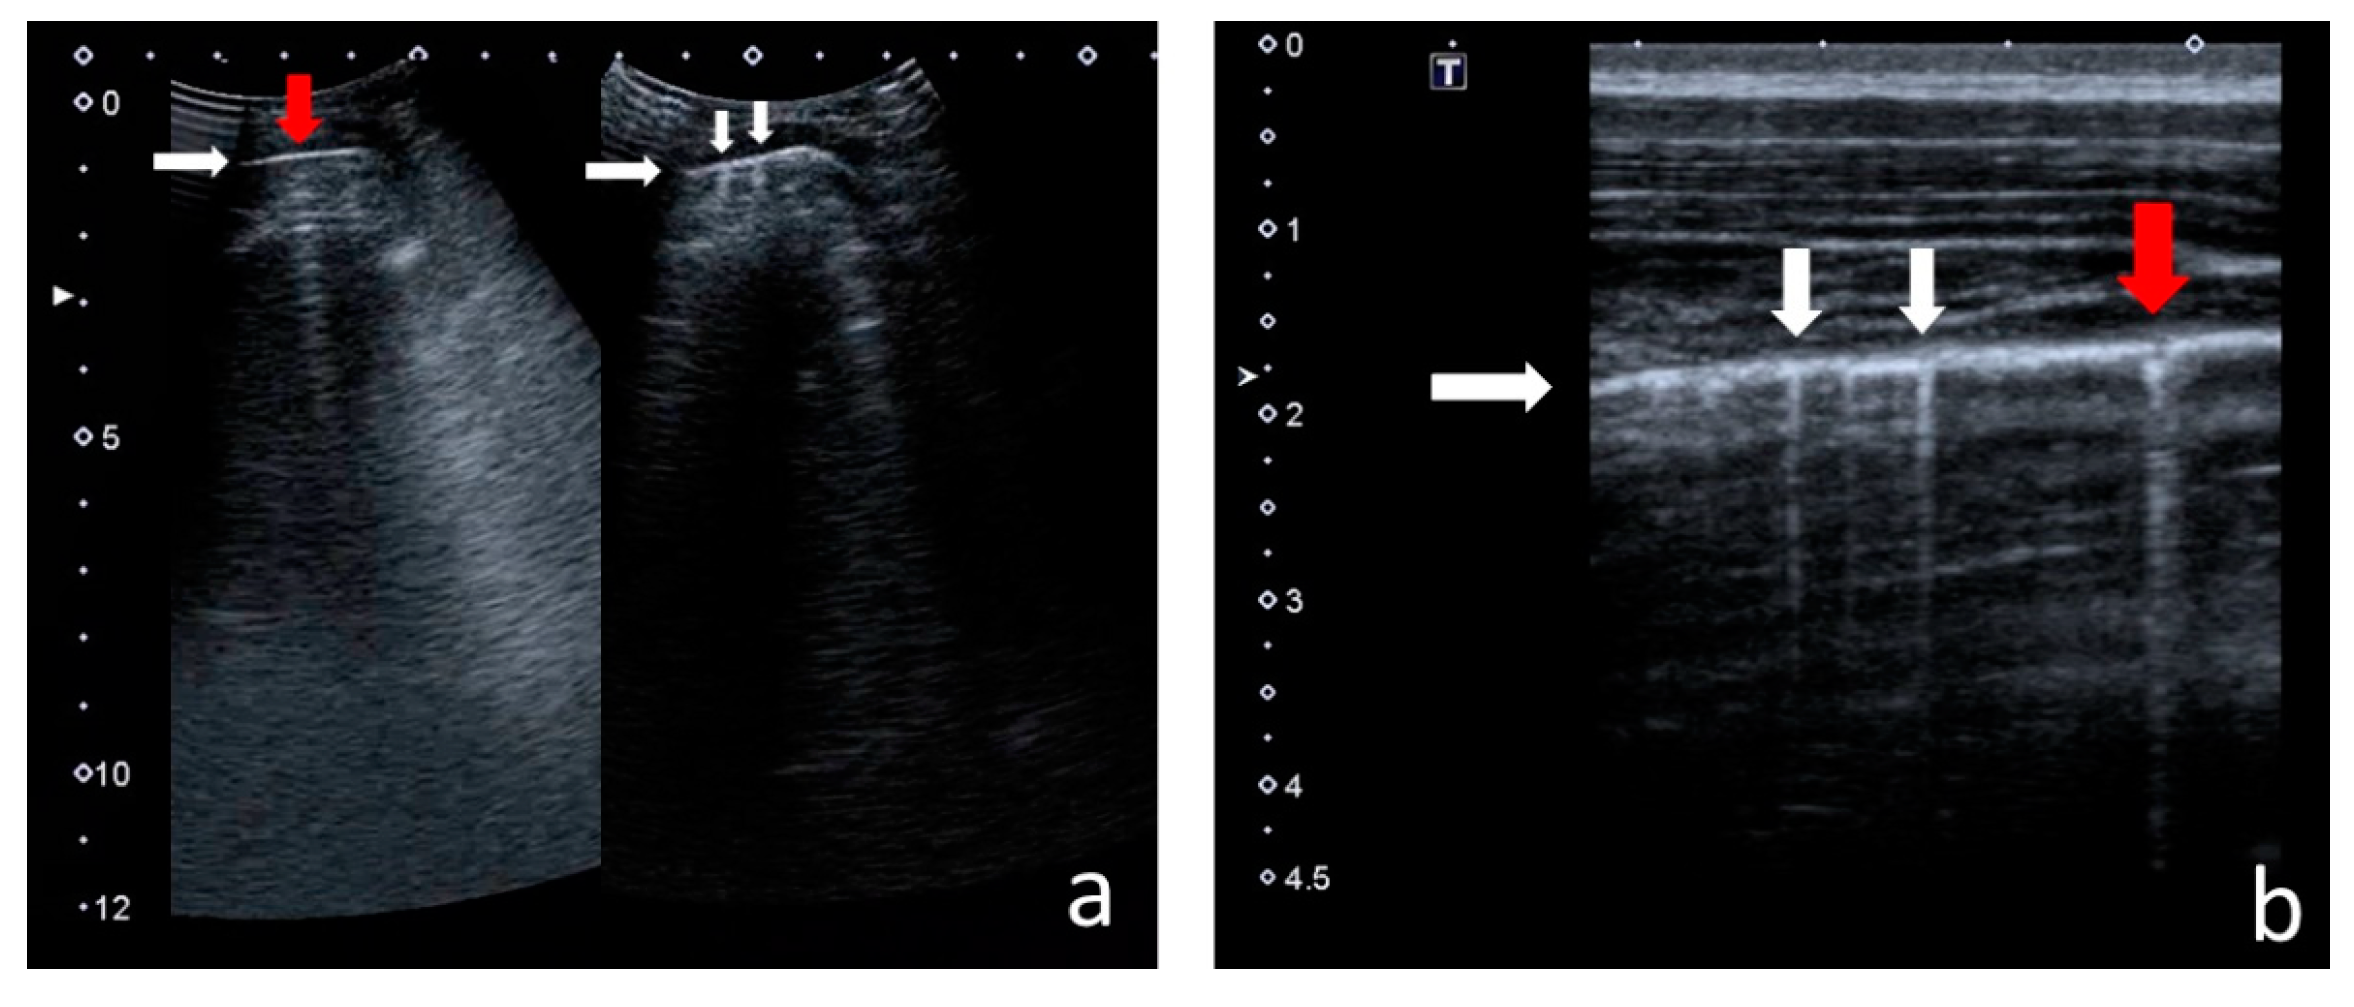

- Consolidations—hypoechoic, tissue-like areas: (a) small (≤10 mm) (Figure 6), and (b) major (>10 mm) (Figure 7); usually, major consolidations have the following associated features: the loss of pleural line echogenicity over the area of consolidation, absence of A-lines, presence of dynamic or static air bronchogram/air trapping and vascular pattern (in CD option) within the area, C-lines below the area, B-lines surrounding it [17,31];